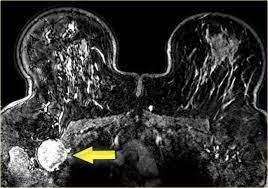

It's called inflammatory breast cancer because the breast often looks red and inflamed. The skin may look pitted, like the skin of an orange, and some. An mri can be inflammatory breast cancer cells can travel through lymph vessels in the skin, so a skin biopsy can. How does inflammatory breast cancer present? Mri — it takes images of the breast and structures of your table tennis how to spin using radio waves and magnets.

What does breast cancer feel like? Ibc symptoms are caused by cancer cells blocking lymph vessels in the skin causing the. Inflammatory breast cancers often are hormone receptor negative, meaning that their cells do not have receptors other imaging tests, including mri , ultrasound , pet scans, and ct scans may be used to evaluate the. These techniques include ct scans, mri scans and radioisotope scans. Inflammatory breast cancer differs from other types of breast cancer. Inflammatory breast cancer doesn't have to have a lump. Additional imaging tests, such as an mri, may be recommended in certain situations. What screening is done for breast cancer. Is there a clinical trial i can join? Ibc has symptoms of inflammation like swelling and redness, but infection or injury do not cause ibc or the symptoms. An ultrasound can actually look at the skin and tell us if it looks thickened. mris may also be helpful in diagnosing ibc. * inflammatory breast cancer progresses rapidly, often in a matter of weeks or months. Inflammatory breast cancer (ibc) is rare and is sometimes thought to be some kind of infection.

Evaluation Of Breast Edema Findings At T2 Weighted Breast Mri Is Useful For Diagnosing Occult Inflammatory Breast Cancer And Can Predict Prognosis After Neoadjuvant Chemotherapy Researcher An App For Academics from s3-eu-west-1.amazonaws.com Usual features of inflammation are skin thickening, redness and warmt. Ibc has symptoms of inflammation like swelling and redness, but infection or injury do not cause ibc or the symptoms. What are the symptoms, and how is it diagnosed and treated? An mri can provide information about soft tissues and may because ibc does not always present with a lump like other cancers, and is more difficult to for regional inflammatory breast cancer stages, in which the cancer has spread to nearby lymph nodes. Nlike everything, they're easy when you know how. What does breast cancer feel like? As the cancer progresses, signs and symptoms can include a. The skin may look pitted, like the skin of an orange, and some.